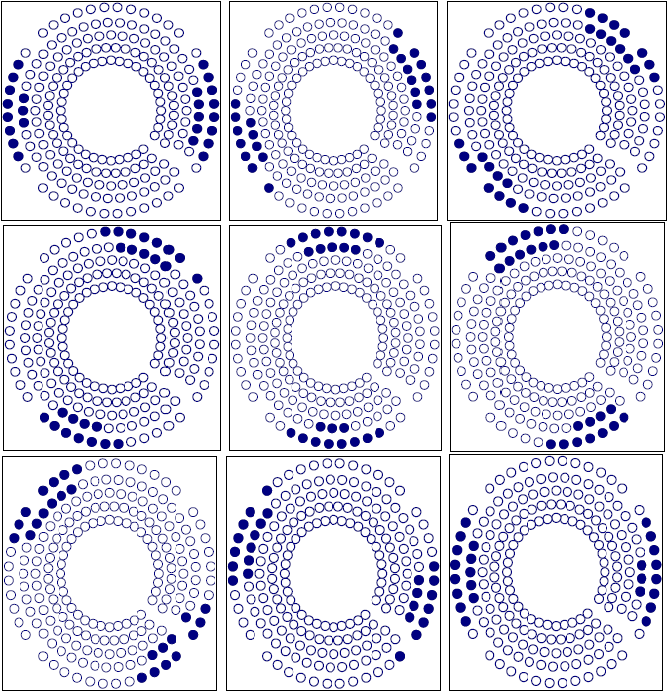

Figure 7 shows the sample point effect on the integral dose calculation by three different trials. The calculation converges at about 100,000 sample points. The number of sample points is determined using an exponential formula. In this setup, we used the integral dose that was calculated by the Monte Carlo method to test the target variation effect on the treatment plan. The Gamma Knife treatment planning system was selected due to the fixed number of beams (201) and fixed geometry of those beams. After checking the convergence of the Monte Carlo calculation, we employed this method to show the sensitivity of the integral dose in beam selection. We fabricated a nine shot Gamma Knife treatment plan with the shot centers midway between inside and outside rings. With a sequence blocking beam treatment for each shot selected, 24 beams were selected to block. There are different possibilities for target variation. A typical case would be the displacement of a target such as an organ at risk. Figure 8 shows three different blocking patterns. Figure 8(a) shows an original setup with 9 plugging shots. Figures 8(b) and 8 (c) show the plugging patterns after the critical structure has been shifted 2 mm superiorly or inferiorly. We developed several mechanisms to compare the different plugging patterns in both the DVH's and treatment patterns. In figure 9, the upper DVH shows the difference due to structure displacement. The circles represent the DVH of the critical region without displacement. The triangles represent the DVH resulting when the critical region is shifted superiorly 2 mm, and the squares represent the situation when the critical region is shifted inferiorly 2 mm. When a blocking beam pattern is used for the treatment, the DVH curves show two features: in one, the dose in the critical structure is significantly lower; in the other, the difference in the three DVH curves decreases and DVH curves nearly overlap each other due to selection of blocking beams. Obviously, displacement of the target leads to variation in the treatment setup. The target DVH curves are not shown because they are overlapped and almost identical for the given resolution in figure 9.

Figure 8a Plugging Pattern of a 9 shot treatment without displacement of the critical structure.

Figure 8b Plugging Pattern of a 9 shot treatment with the critical structure displaced 2 mm superiorly.

Figure 8c Plugging Pattern of 9 shots treatment with the critical structure displaced 2 mm inferiorly.